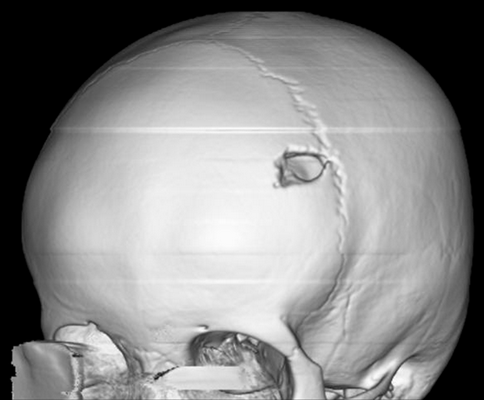

Молодой человек 17 лет был госпитализирован по поводу увеличивающегося в течение последних 6 недель образования волосистой части головы. Образование при пальпации болезненно, из‑за изъязвления периодически кровоточит, однако неврологического дефицита не выявлено. При КТ и МРТ выявлен крупный очаг в лобной кости справа, сдавливающий верхний сагиттальный синус. Проведена тотальная резекция образования, подтвержден диагноз «лангергансоклеточный гистиоцитоз кости черепа». На амбулаторном этапе проводилась терапия цитостатиком.

Рисунок 6. (а) КТ-исследование без контрастирования — фронтальное сканирование (верхняя и средняя часть) и 3D-реконструкция черепа (нижняя часть). (b) МРТ-сканирование. Т1‑взвешенное изображение во фронтальной плоскости (сверху) и Т2‑взвешенное изображение в сагиттальной плоскости